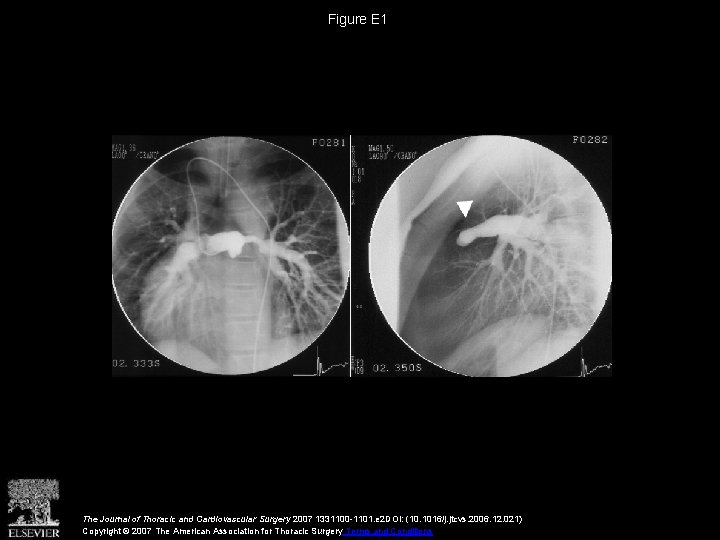

Figure E 1 The Journal of Thoracic and Cardiovascular Surgery 2007 1331100 -1101. e

Figure E 1 The Journal of Thoracic and Cardiovascular Surgery 2007 1331100 -1101. e 2 DOI: (10. 1016/j. jtcvs. 2006. 12. 021) Copyright © 2007 The American Association for Thoracic Surgery Terms and Conditions